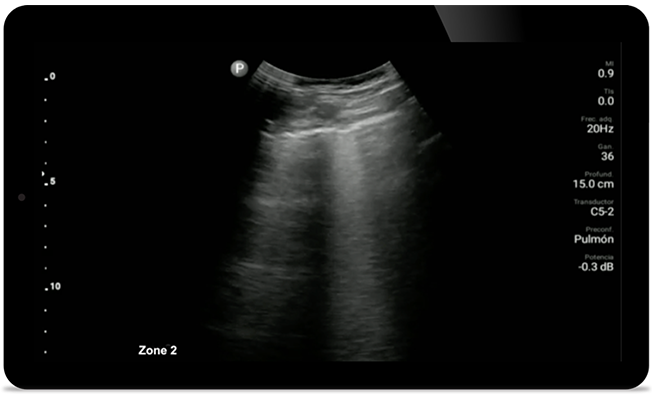

Fiţi cu ochii pe pneumonia provocată de COVID

Lumify poate contribui la obţinerea unor rezultate similare cu cele ale unui CT toracic atunci când se evaluează pneumonia şi sindromul de detresă respiratorie la adulţi.